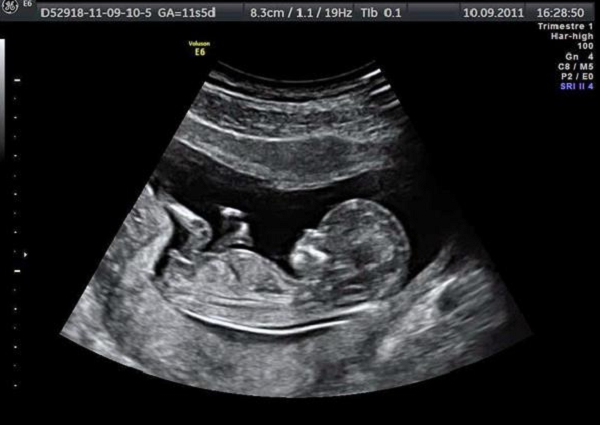

Hình ảnh siêu âm thai nhi 18 tuần có nhiều bất ngờ

- Qua hình ảnh siêu âm mẹ có thể thấy cơ thể bé vô cùng hiếu động. Tư thế bé như đang tập yoga với lưng thẳng, đôi chân gấp lại. Bé cũng có thể uốn lượn hay duỗi tay chân một cách tinh nghịch. Ngay cả khi không siêu âm mẹ cũng có thể cảm nhận được chuyển động này của bé.

- Bé cũng hay cho tay vào miệng ngậm hay xoa chân vào nhau. Qua hình ảnh siêu âm mẹ có thể thấy bé rất đáng yêu.

- Siêu âm cũng thấy bánh nhau nằm ở đáy tử cung và được gắn kết chặt chẽ với thành tử cung. Bánh nhau sẽ lớn dần theo sự phát triển của bé. Tuy nhiên, bánh nhau không phải lúc nào cũng cố định một chỗ.

Hình ảnh siêu âm thai nhi 18 tuần tuổi